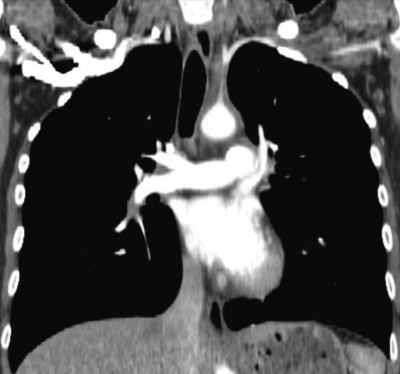

血液所見:赤血球 403 万、Hb 10.0 g/dL、Ht 30 %、白血球 10,900 (桿状核好中球 28 %、分葉核好中球 47 %、好酸球 1%、好塩基球 1%、単球 7%、リンパ球 16%)、血小板 46 万。血液生化学所見:尿素窒素 13 mg/dL、クレアチニン 0.5 mg/dL。免疫血清学所見:CRP 11 mg/dL、抗核抗体陰性、リウマトイド因子<RF>陰性。胸部造影 CT の水平断像及び冠状断像を別に示す。